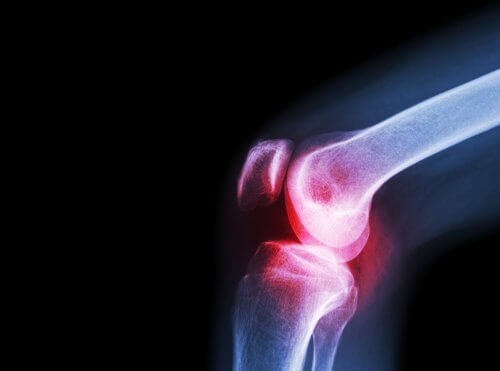

Aceclofenac zur Behandlung von Arthrose

Auch bei Arthrose kommt Aceclofenac zum Einsatz. Dazu kommt es, wenn der Knorpel irreparabel geschädigt wird, was zu einer Reibung der Knochen in den Gelenken führt. Im Inneren des Gelenkes befindet sich die Synovialflüssigkeit, die von der Synovialhaut produziert wird. Die Knochenenden sind von Knorpelgewebe überzogen, das wiederum von der Synovialflüssigkeit getränkt wird.

Wenn jedoch der Knorpel geschädigt wird, können die Zellen nicht mehr neu gebildet werden. In der Folge kommt es zu Schmerzen, Steifheit und zu funktioneller Unfähigkeit. Es ist jedoch wichtig, diese Krankheit von Arthritis zu unterscheiden. Zu Arthritis kommt es durch eine Gelenksentzündung, nicht durch die Abnutzung des Knorpels.